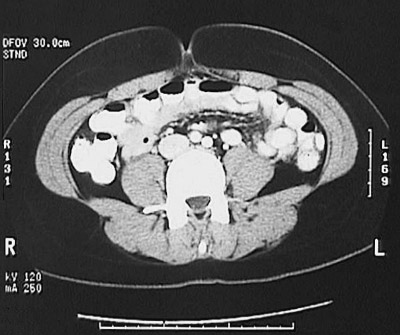

[L4] This is a normal abdominal CT scan with contrast demonstrating the abdomen with the ascending colon and descending colon and small intestine and inferior vena cava and right common iliac artery and left common iliac artery and right ureter and left ureter and psoas muscle and sacrospinalis muscle and multifidus muscle and external oblique muscle and internal oblique muscle and umbilicus .